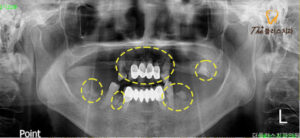

전치부와 하악 소구치 2개만 잔존해 있고

나머지 치아는 상실되거나

치근만 남아있는 상태였습니다.

하악에는 좌측 소구치를 제외한

나머지 치아는 다행히 치조골의 상태가 양호하고

치아를 보존하여 사용해도 괜찮을 것 같아서

브릿지로 연결하여 사용하기로 하였습니다.